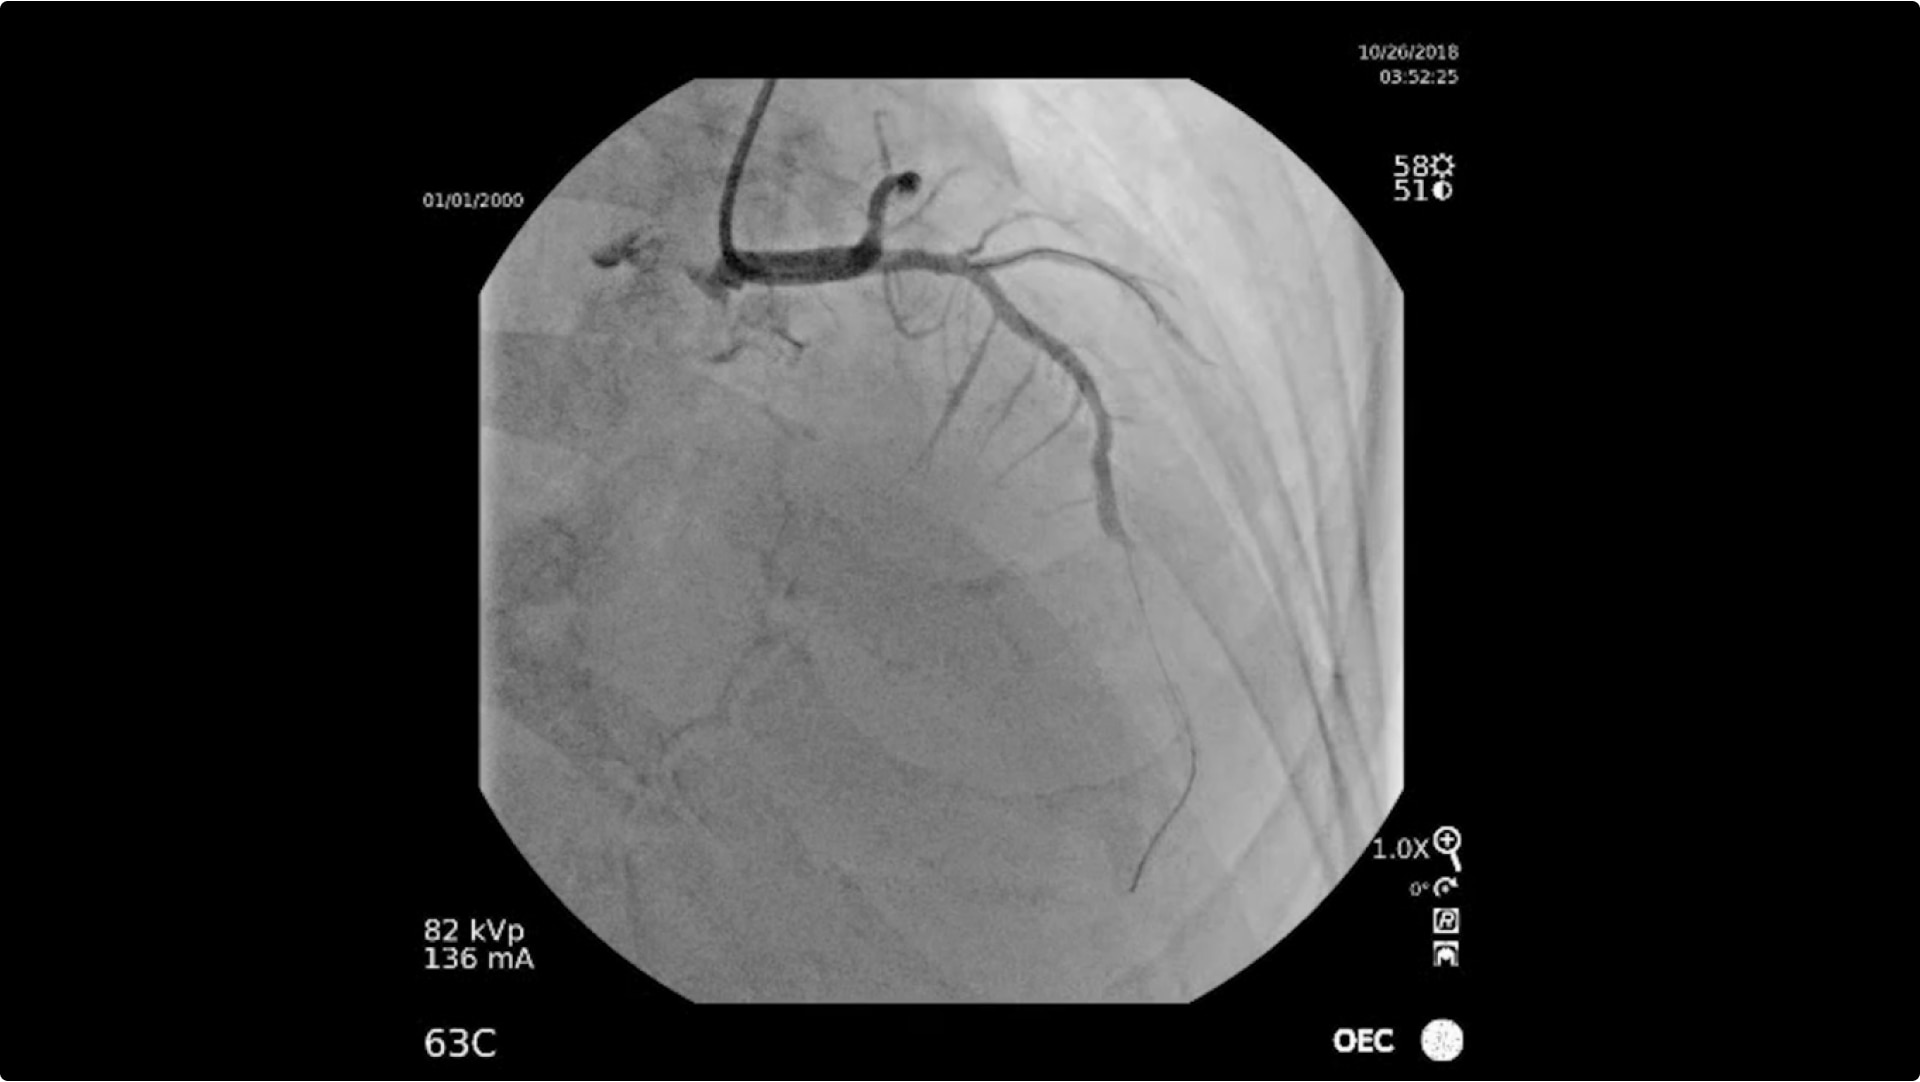

• Diagnostik der Koronararterien

• Perkutane transluminale Angioplastie

• Koronar-Stenting